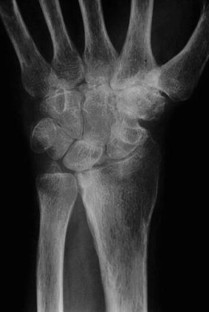

Fig. 2.